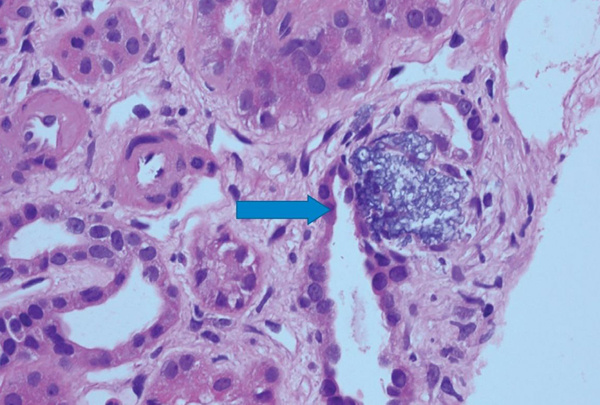

Такие случаи не частые, когда витамин D бывает токсичным, однако, его избыток в организме может вызвать повышение в крови кальция - гиперкальциемию. Именно это и случилось с мужчиной из Канады. По возвращению из отпуска в Юго-Восточной Азии он обратился в больницу. Анализы показали превышение уровня креатинина, а это один из основных показателя качества работы почек. Клинический случай описан в Canadian Medical Association Journal. Семейный врач настоял на отмене приема лекарств от подагры и мочегонных препаратов. Через месяц повторные анализы не показали улучшений. Работа почек ухудшилась в разы. Проведя тщательное обследование медики не поставили диагноз, т.к. почки оказались абсолютно здоровы. Но все еще обнаруживался высокий уровень кальция и наличие паратиреоидного гормона, который регулирует выведение кальция из организма. Подобное наблюдается при избытке витамина D. Выяснилось что пациент по назначению натуропата 2.5 года принимал высокие дозы витамина D. Состояние здоровья